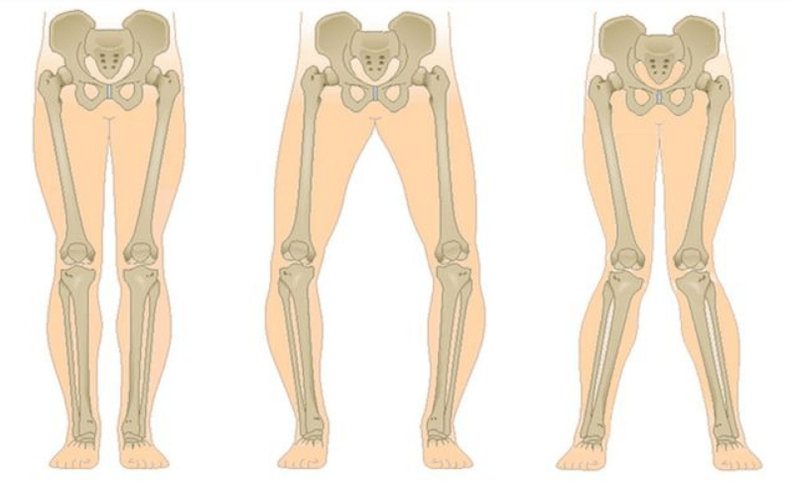

The final stage of gonarthrosis is distinguished by the fact that the pain is almost constant, causing discomfort not only during walking, but also during rest, even at night when patients have to look for a comfortable position to sleep.Movement is more limited: it is difficult to fully bend and straighten the leg.The joint deforms and increases in volume.Valgus (X-shaped) or varus (O-shaped) deformation of the legs is often observed.His gait is unsteady and wobbly.In severe cases, a cane or crutches are needed.

Unilateral and bilateral gonarthrosis are distinguished depending on the number of affected joints.